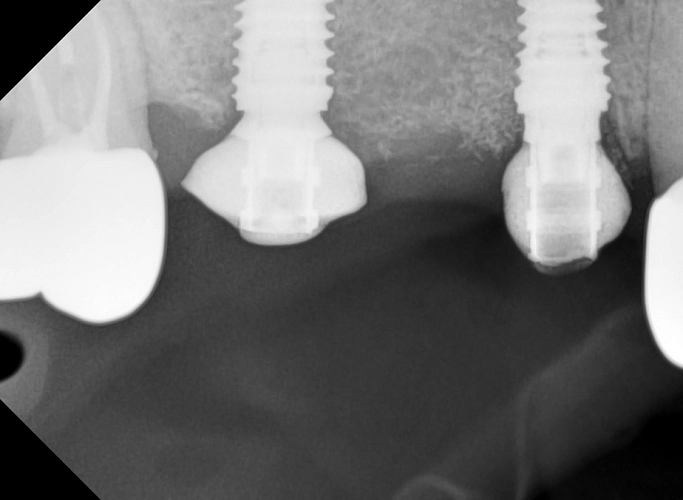

На фото — работа нашего врача-хирурга-имплантолога Федотова Руслана Валерьевича. В этом случае была успешно проведена имплантация с синус-лифтингом — процедурой, которая позволяет поднять дно гайморовой пазухи и создать необходимое пространство для установки импланта.